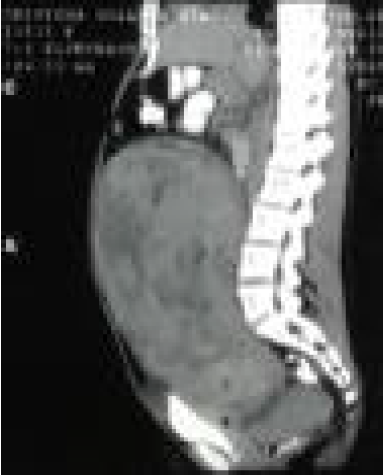

TAC abdomino-pélvica: vejiga comprimida, útero aumentado de tamaño de 22,7 x 21,7 x 25 cm heterogéneo, en adquisiciones simples y tras la colocación de contraste endovenoso con áreas hipodensas de aspecto necrótico y muy vascularizado (figura 2), condicionando desplazamiento de estructuras anatómicas adyacentes especialmente vejiga y asas intestinales, tumoración con crecimiento rápido. Ampolla rectal normal. Útero aumentado de volumen con aspecto miomatoso, sin embargo, el crecimiento rápido de masas uterinas, sugiere tumor maligno (leiomiosarcoma). Se sugiere biopsia a fin de precisar naturaleza de la lesión.

Corte longitudinal en donde se aprecian áreas hipodensas de aspecto necrótico y muy vascularizado, condicionando desplazamiento de estructuras anatómicas adyacentes especialmente vejiga y asas intestinales, útero aumentado de volumen con aspecto miomatoso.